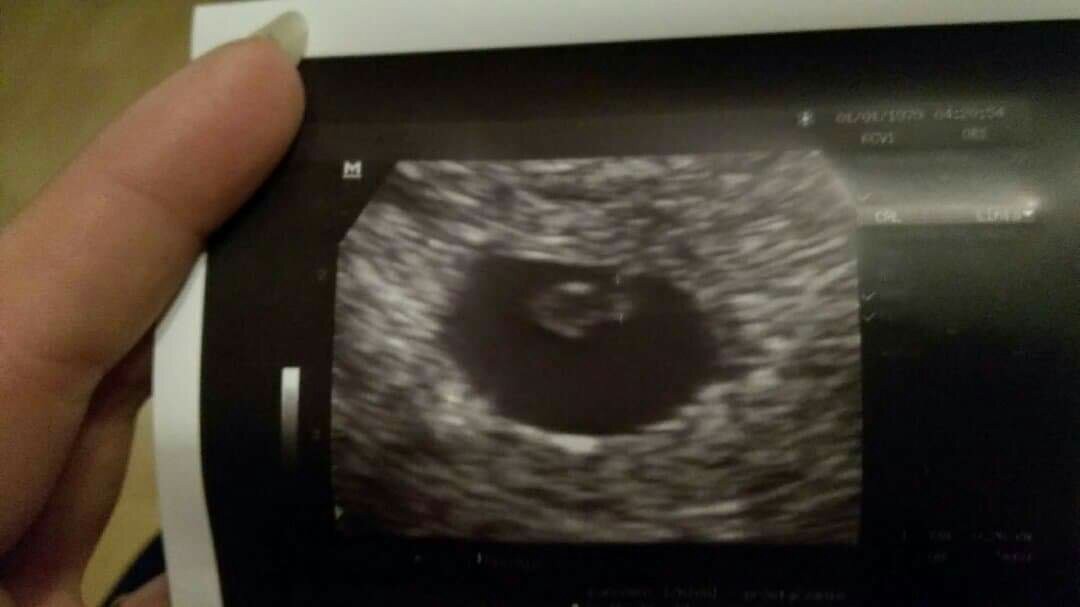

lekarz zrobił usg fasolek jest tylko pow że serduszko za słabo bije 120...zarodek ma 6 tyg, a ja jestem 7tyd2d po krwiaku nie ma śladu i nie wie skąd krwawienie kazał trzymać kciuki